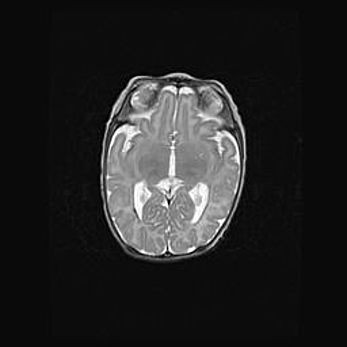

Церебральная ишемия II.

Возраст: 7 дней

Вес: 3350 г

Пол: женский

Окружность головы: 35 см

Срок гестации: 39 недель

Ишемия головного мозга – это состояние, которое развивается в ответ на кислородное голодание вследствие недостаточного мозгового кровообращения. У новорожденных она является следствием дефицита кислорода, что ведет к метаболическим расстройствам различной степени тяжести в тканях головного мозга, в том числе к развитию коагуляционных некрозов и гибели нейронов.